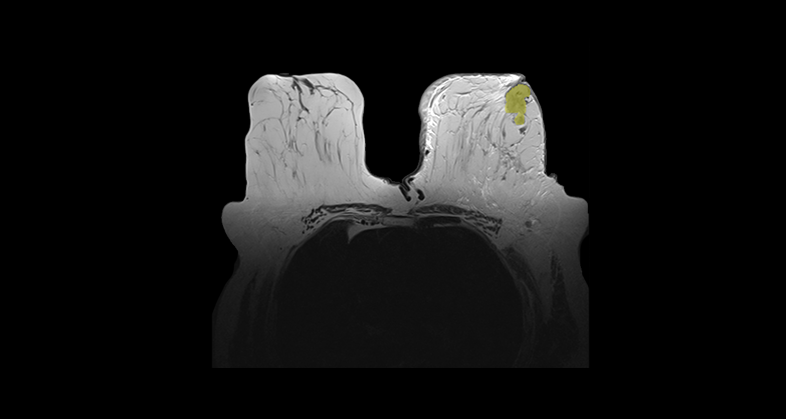

Our AI-based tools provide patients with an early diagnosis for rheumatic diseases in the main imaging modalities. We support the digital transformation of therapy indication either during drug-development phases or in post-approval scenarios, deploying an integrated offering to healthcare providers.

Developing a radiomics-based tool for predicting pathological complete response (pCR) to neoadjuvant chemotherapy in breast cancer